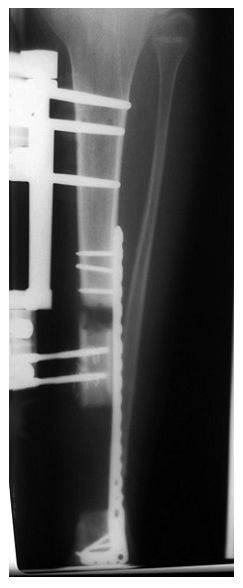

➤ 1、骨科外固定支架单边(用于骨搬运+支撑);

➤ 2、锁定长钢板(维持长度+支撑);

➤ 3、I期术后12个月,搬运到位后,直接上螺钉固定,去除外固定架。

◈ 通过这种内外组合,平均愈合时间是266天,14例患者均取得良好的骨愈合。